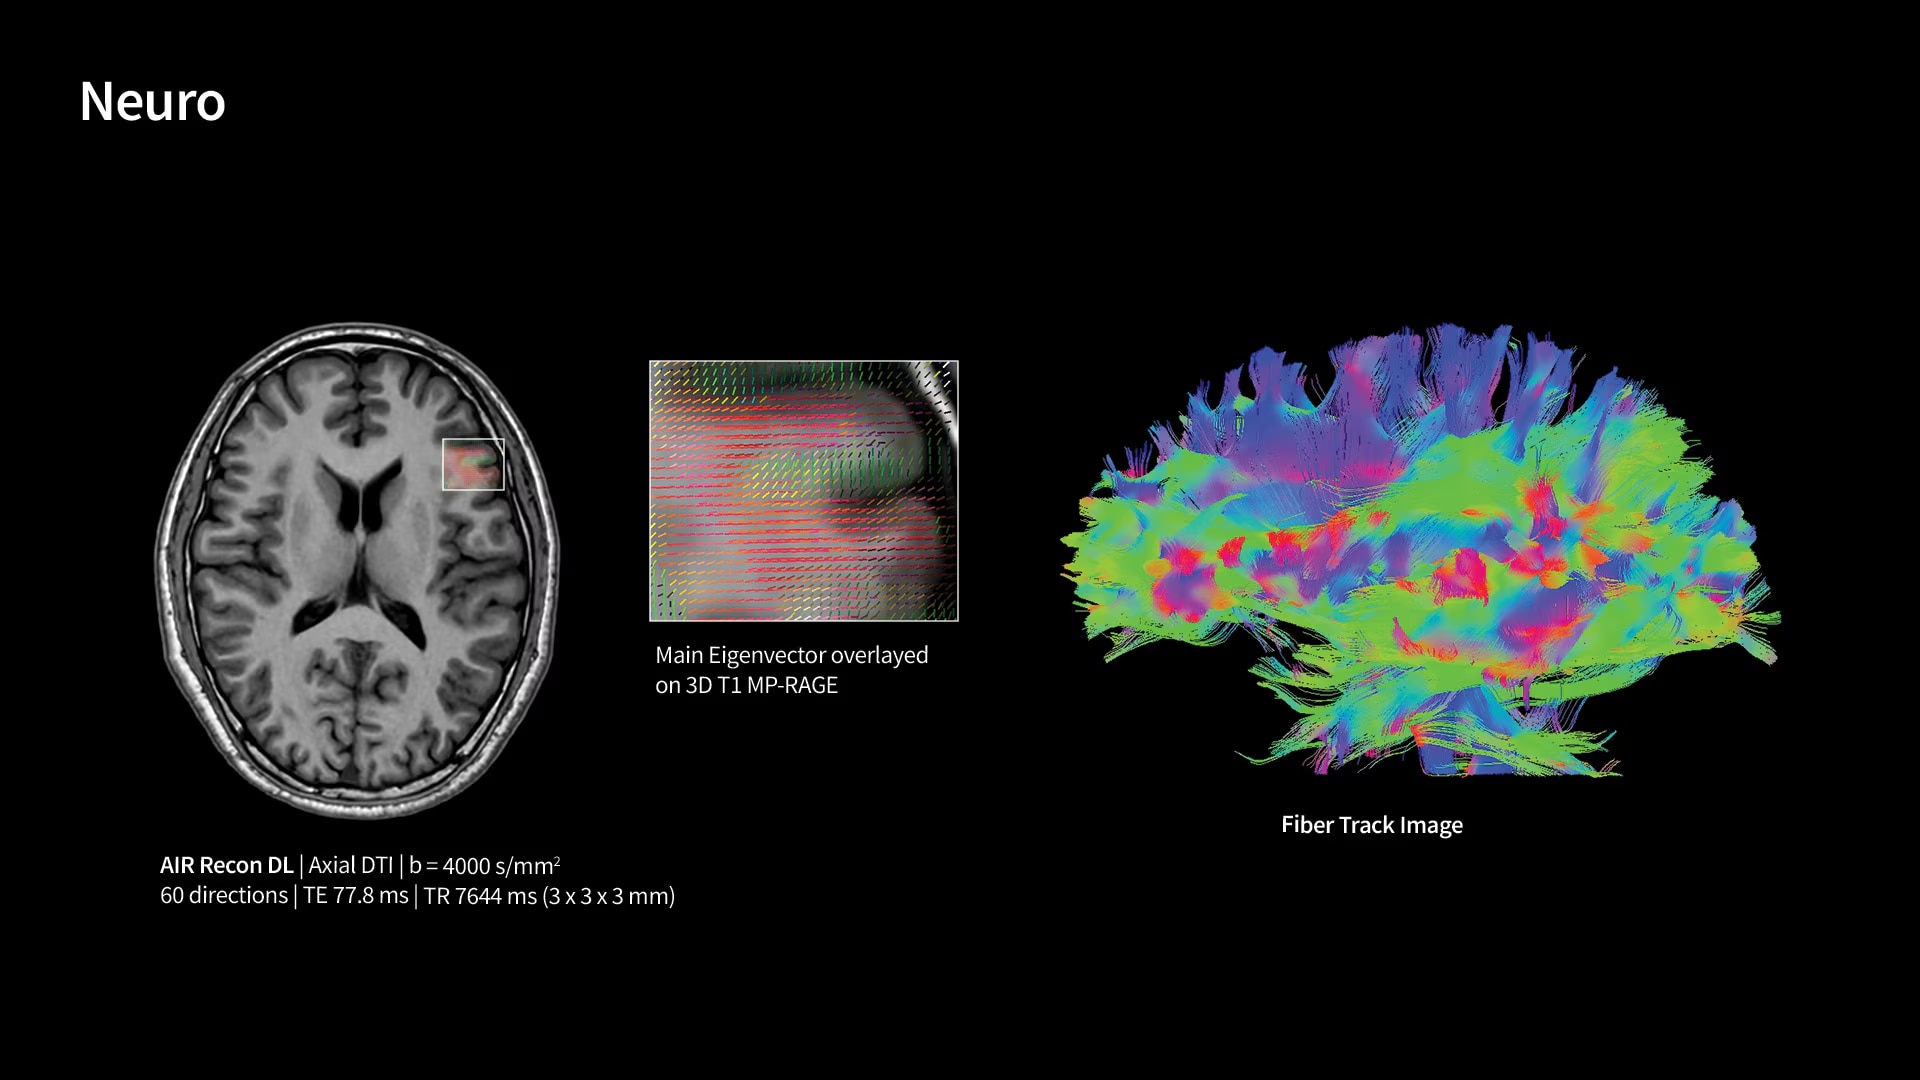

Unlock your potential

With GE HealthCare's comprehensive suite of deep-learning solutions integrated into SIGNA Sprint, you can unlock the full potential of your MRI system. No need for complicated patient setups or imaging protocols. The exceptional intelligence of our AI solutions offer multiple benefits, with AIR Recon DL giving pin-sharp images, Sonic DL accelerating scans up to 12x, and AIR x enabling automated slice placement. All helping to enhance your department’s workflow efficiency, increase patient throughput, and get the diagnostic clarity you need, faster.¹ Meaning you can spend more time on what truly matters—personalized patient care, enabling optimized treatment plans and treatment response monitoring—ultimately, supporting better clinical outcomes.